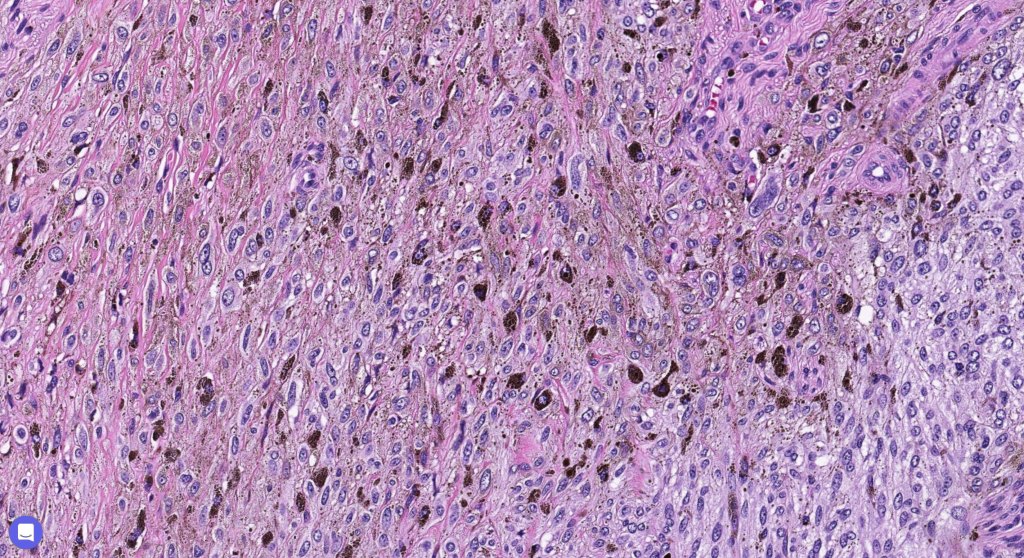

Histologically, it is characterized by a dense population of spindled, dendritic melnanocytes & melanophages with variable fibrosis. It may sometimes represent a component of a combined nevus. Mitotic activity is not usually present and pleomorphism is absent (see atypical blue nevus below). Involvement of the arrector pili muscle is not uncommon.

Very exceptionally, blue nevus also involves the epidermis (compound blue nevus).